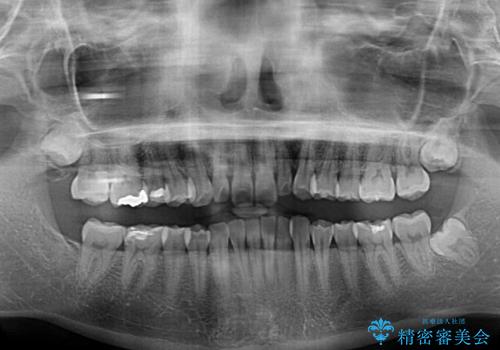

- 前歯の歯並びと生えてきたときから小さい前歯を気にして来院された患者様です。

上下前歯の歯列不正はインビザラインにより整え、その後に、矮小歯の前歯をオーダーメイドタイプのオールセラミッククラウンにて補綴治療することとしました。